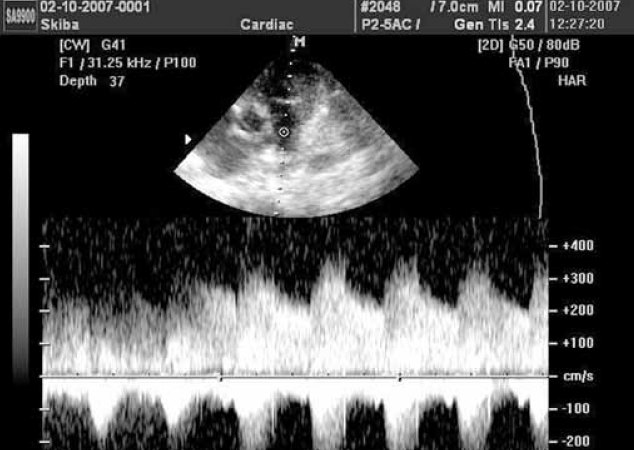

Восемь детей с наличием перекрестного сброса через ОАП в 100 % случаев наших наблюдений являлись недоношенными и имели повышенное давление в легочной артерии за счет бронхолегочной дисплазии (БЛД). ОАП в «стадии закрытия» диагностировался у детей 1-го года жизни старше 4 недель после периода новорожденности. При допплерографии ствола легочной артерии регистрируются волнообразные эпизоды практически полного отсутствия сброса через ОАП, сменяющиеся периодами нарастания сброса, сопровождающиеся появлением классической аускультативной картины (рис. 1).

Рис. 1. Допплерография ствола легочной артерии. Запечатлен эпизод значительного возрастания сброса через открытый артериальный проток, сопровождавшийся появлением систоло-диастолического шума